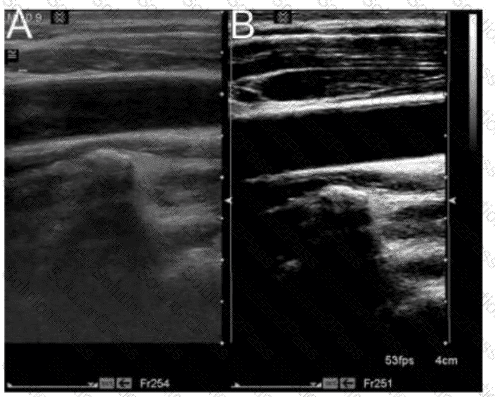

In this image, which characteristics of flow are represented by the upper right side of a variance mode color map?

A.

Higher velocity, laminar with a positive Doppler shift

B.

Higher velocity, laminar with a negative Doppler shift

C.

Higher velocity, turbulent with a positive Doppler shift

D.

Higher velocity, turbulent with a negative Doppler shift